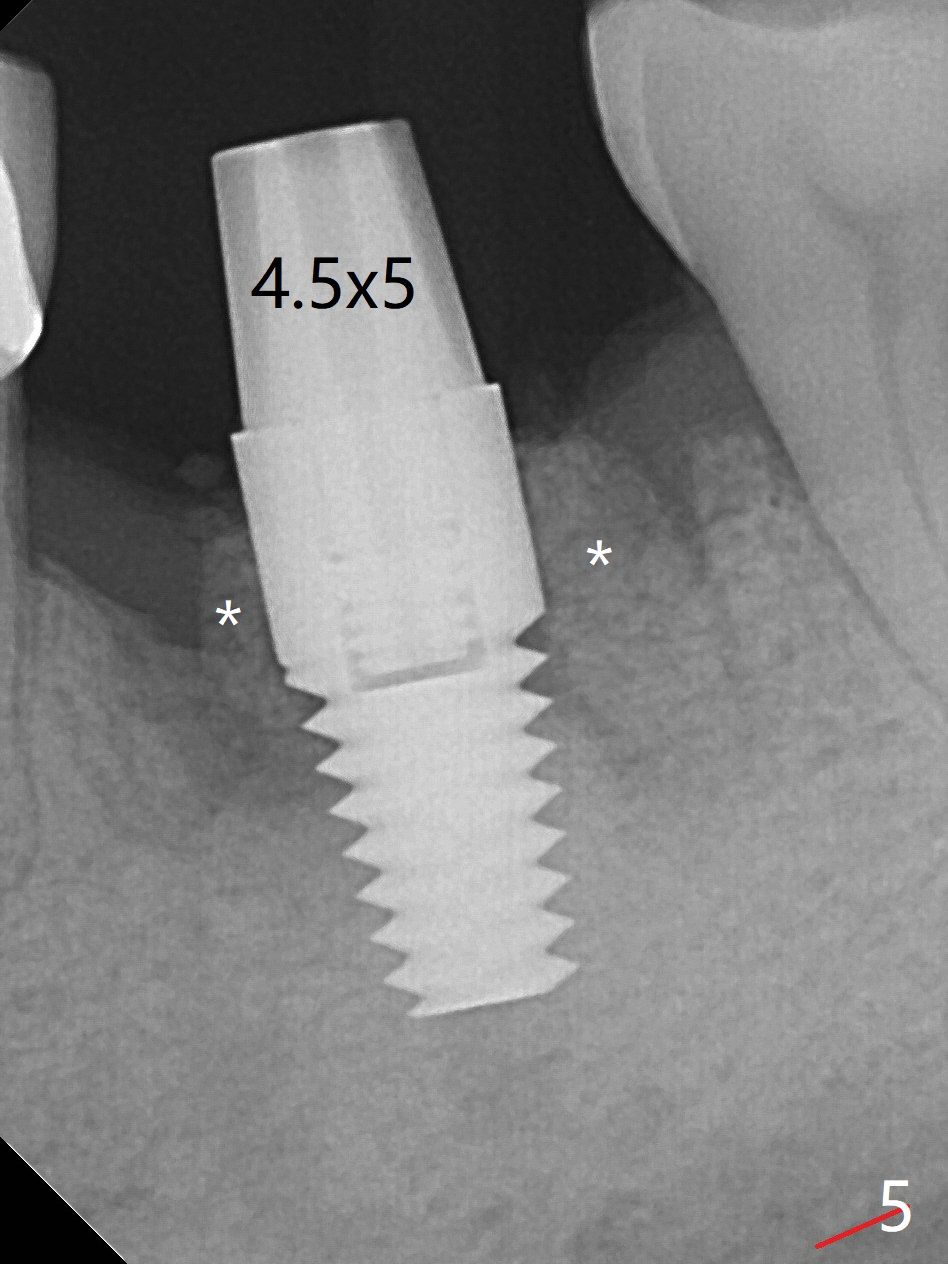

After extraction of the tooth #19 with mesial root fracture (Fig.1 ^) and curettage, the initial osteotomy in the septum is found to need to be distalized (Fig.2 arrow). Following sequential osteotomy, a 5x17 mm tap cannot reach the expected depth (Fig.3 yellow dashed line) because of the dense bone. A shorter implant is placed with >60 Ncm (Fig.4). An immediate provisional is fabricated after placement of a 4.5x5 mm abutment and Vanilla/Osteogen graft (Fig.5 *). The mesial and distal sockets heal 4 months postop (Fig.6). The bone density in the mesial and distal sockets continues to increase when a crown is cemented (~4.5 months postop, Fig.7). The implant at #19 was placed in the middle of the bone (Fig.8).